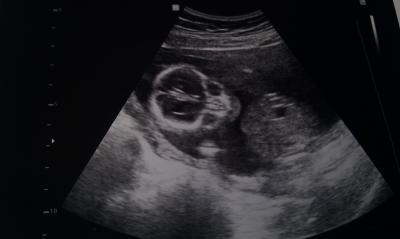

Und nach dem halloween Bildchen noch eins von der Seite....

Bild zu

hihi das erste is cool u des zweite voll süß, tolle pausbäckchen! glückwunsch zum jungen!!!!! schön das es dem babymann gut geht!